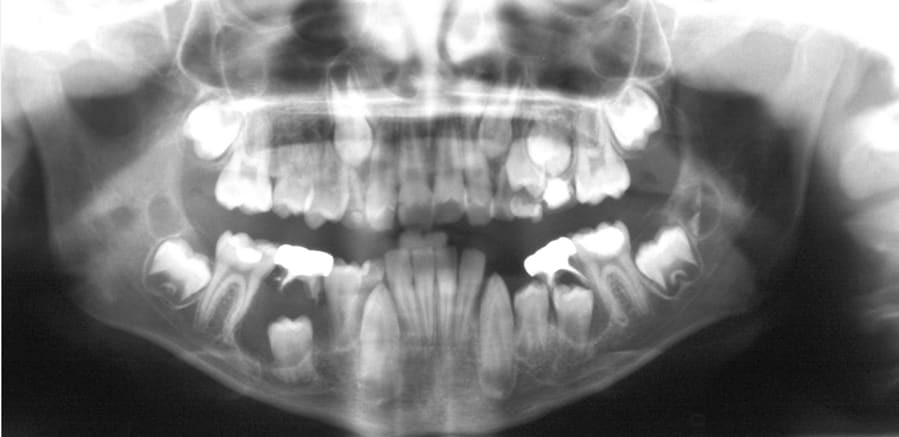

How is it diagnosed?

Small dentigerous cysts often go unnoticed until you have a dental X-ray. If your dentist notices an unusual spot on your dental X-ray, they may use a CT scan or MRI scan to make sure it’s not another type of cyst, such as a periapical cyst or an aneurysmal bone cyst.

In some cases, including when the cyst is larger, your dentist may be able to diagnose a dentigerous cyst just by looking at it.